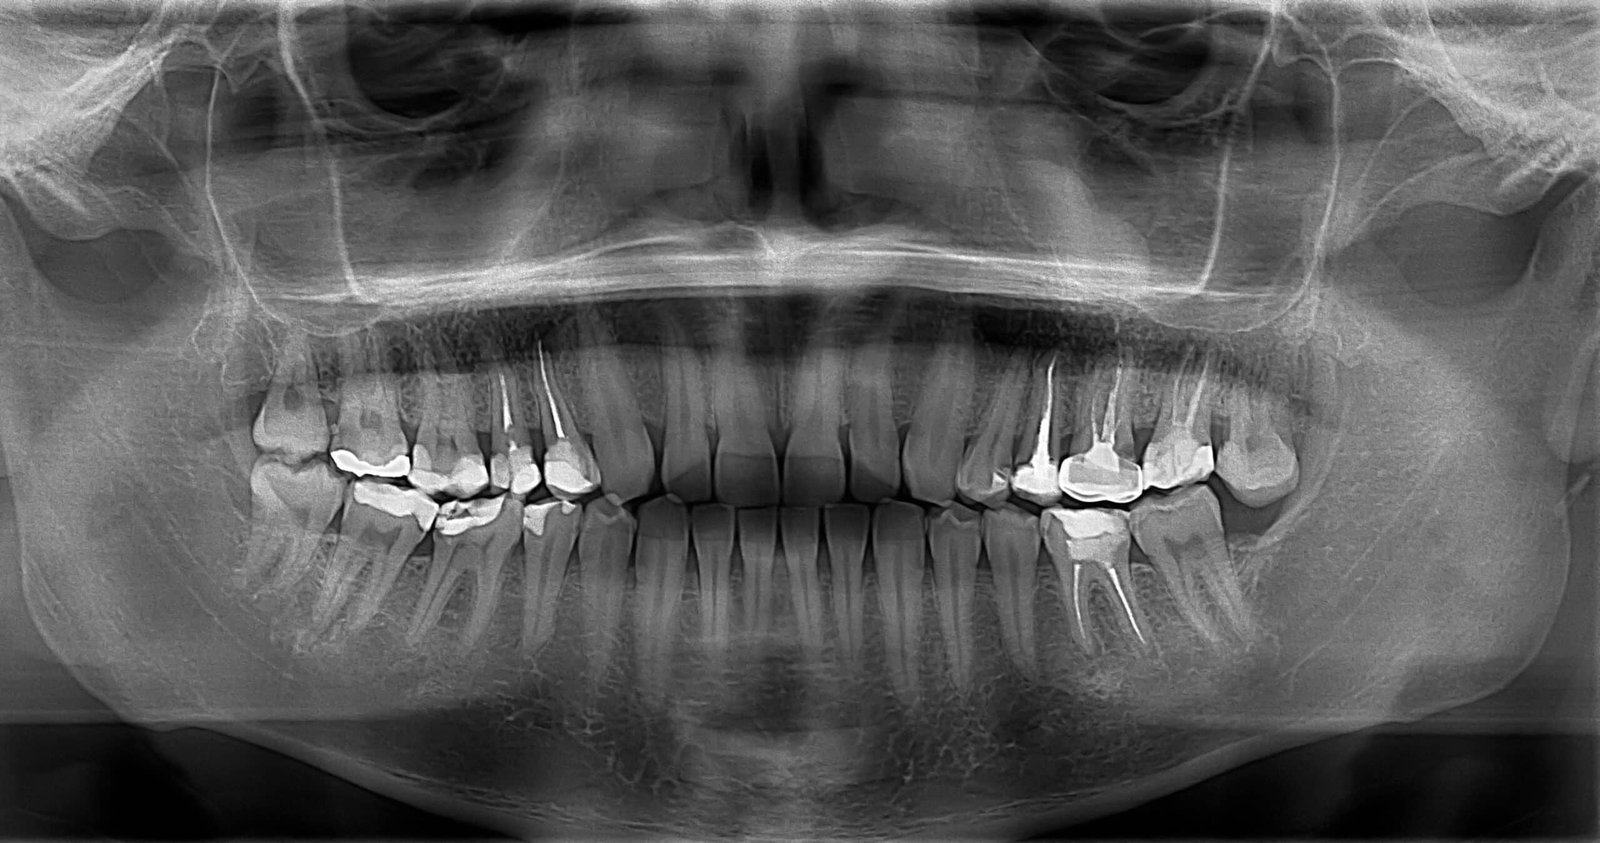

Eine Wurzelkanalbehandlung oder auch Wurzelbehandlung ist oft die letzte Möglichkeit, einen entzündeten oder abgestorbenen Zahn zu erhalten. Dabei wird das erkrankte Gewebe aus dem Inneren des Zahns entfernt, die Wurzelkanäle werden gründlich gereinigt, desinfiziert und anschließend dicht verschlossen. Dank moderner Verfahren lässt sich ein Zahn, der früher verloren gegangen wäre, heute langfristig retten.

Bei einer Wurzelkanalbehandlung öffnen wir den Zahn vorsichtig, um das entzündete oder abgestorbene Nervengewebe zu entfernen. Mit Hilfe eines Mikroskops und spezialisierter Nickel-Titan-Instrumente reinigen und formen wir die Kanäle gründlich, bevor sie mit modernen Materialien dicht verschlossen werden. Diese Therapie – auch Endodontie genannt – verhindert, dass Bakterien im Zahn verbleiben und eine erneute Entzündung auslösen.

Eine Wurzelkanalbehandlung ist immer dann notwendig, wenn der Zahnnerv entzündet oder abgestorben ist – meist verursacht durch tiefe Karies, Zahnverletzungen oder Risse. Typische Anzeichen sind starke Schmerzen, Empfindlichkeit beim Kauen oder Schwellungen am Zahnfleisch. Ohne Behandlung kann sich die Entzündung ausbreiten und den Zahn irreversibel schädigen.

Mit Hilfe von Endodontie Leipzig, also mikroskopischer Wurzelkanalbehandlung, entfernen wir das entzündete Gewebe vollständig, reinigen die Kanäle gründlich und verschließen sie bakteriendicht. So lassen sich selbst stark geschädigte Zähne noch viele Jahre erhalten.